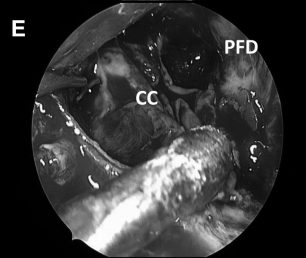

▼解剖、剥离并切除肿瘤包膜(D、E)

▼(L)使用鼻中隔瓣 (NSF)完成封闭。CC,囊包膜;PFD,后颅窝硬脑膜;S,蝶鞍;T,肿瘤。